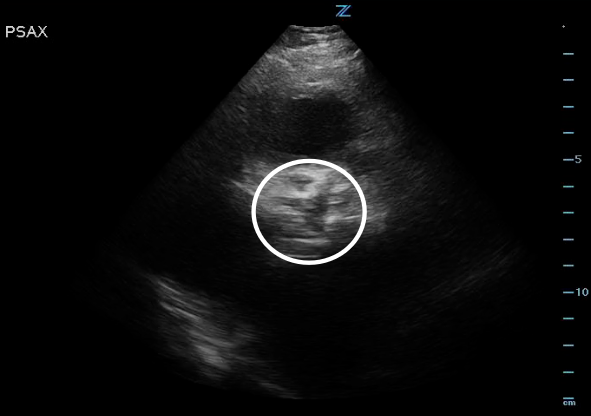

Figure 2. High PSAX (RVOT) view of the AV orifice (circled) closed.

Figure 3. High PSAX (RVOT) view of the AV orifice (circled) open.

- Obtain a parasternal long axis (PLAX) and right ventricular outflow view (RVOT) and examine the aortic valve leaflets. Is there AV calcification? How’s the AV leaflet mobility? Is there also LV hypertrophy? Several studies have found that novice sonographers have been able to accurately pick up severe aortic stenosis.4-6

*Notice how calcified the AV leaflets are and how little the valve orifice opens.